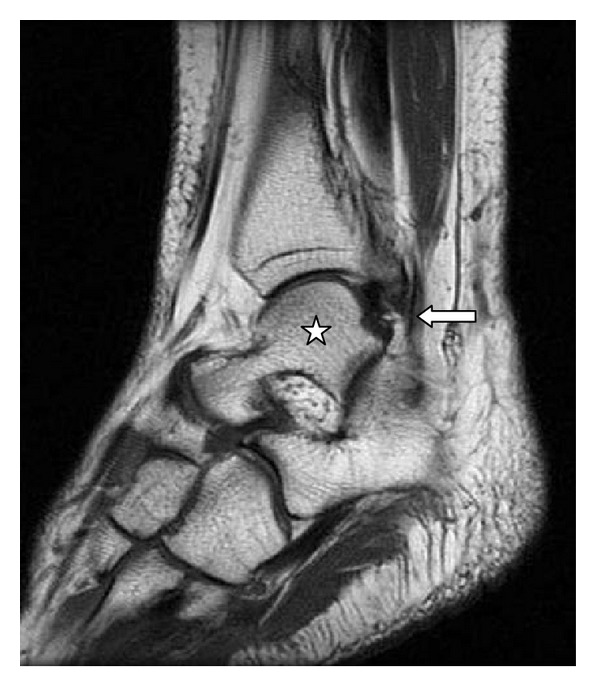

Objective. Quantify the presence of the fibularis quartus muscle and correlate it with the individual's sex and concomitant presence of the fibularis tertius muscle. Materials and Methods. We evaluated 211 magnetic resonance examinations (43.13% men and 56.87% women) on the ankle and hindfoot, produced between 2009 and 2011. Results. The fourth fibularis muscle was found to be present in 7.62% of the examinations and 75% of these also contained the fibularis tertius muscle. Conclusion. The incidence of the fourth fibularis muscle is variable; moreover, its incidence does not depend on the individual's gender or the presence of the fibularis tertius muscle.